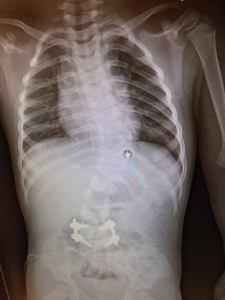

My husband and I noticed Carson’s spine appeared to be curved when he was just 5 months old. I brought up our concerns to his pediatrician at his 6 month appointment. She dismissed our concerns, saying babies are just flexible and they don’t have very strong muscles to hold themselves properly. When Carson was 10 months, he was having testing done for another medical condition. During that test my husband asked the radiologist to shoot a film of his spine because we were so certain he had scoliosis….and there it was…a very obvious “s” shaped curve, 60 degrees thoracic and 45 degree lumber. With that we started our research.

We started with a local orthopedic doc where we lived. We knew that this wouldn’t be the doc to manage him long term, but we wanted to get things started. He did an x-ray and told us Carson had a congenital defect, a hemivertebrae between L4-L5. A couple weeks later Carson had an MRI and CT done under general anesthesia. We looked for docs that were treating a lot of infants with congenital scoliosis. We found that many claimed to specialize in pediatric scoliosis but we wanted a doc that was treating infants and toddlers, not just teenagers.